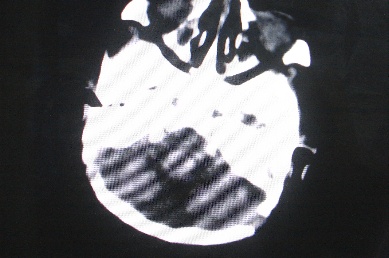

以下是引用余辉在2007-4-30 16:36:00的发言:[br]呵呵,图片不行啊,双肺弥漫斑片状影。右肺门增大,结构模糊。左侧脑室前部室管膜下可见团块状高密度影,周围有低密度环带,左额叶呈大片状低密度改变,略呈楔形,累及灰白质,局部脑沟裂消失,右额叶脑白质亦可见点状病灶(不知是伪影还是真病灶)脑室系统明显扩张,有全脑脑萎缩征象,不知其病史,暂考虑1双肺结核,左额叶结核性脑炎,(左侧脑室前部室管膜下肉芽?出血?)合并脑积水脑萎缩(左额叶低密度区不排除脑梗塞改变)2双肺非特异性炎症合并化脓性脑炎